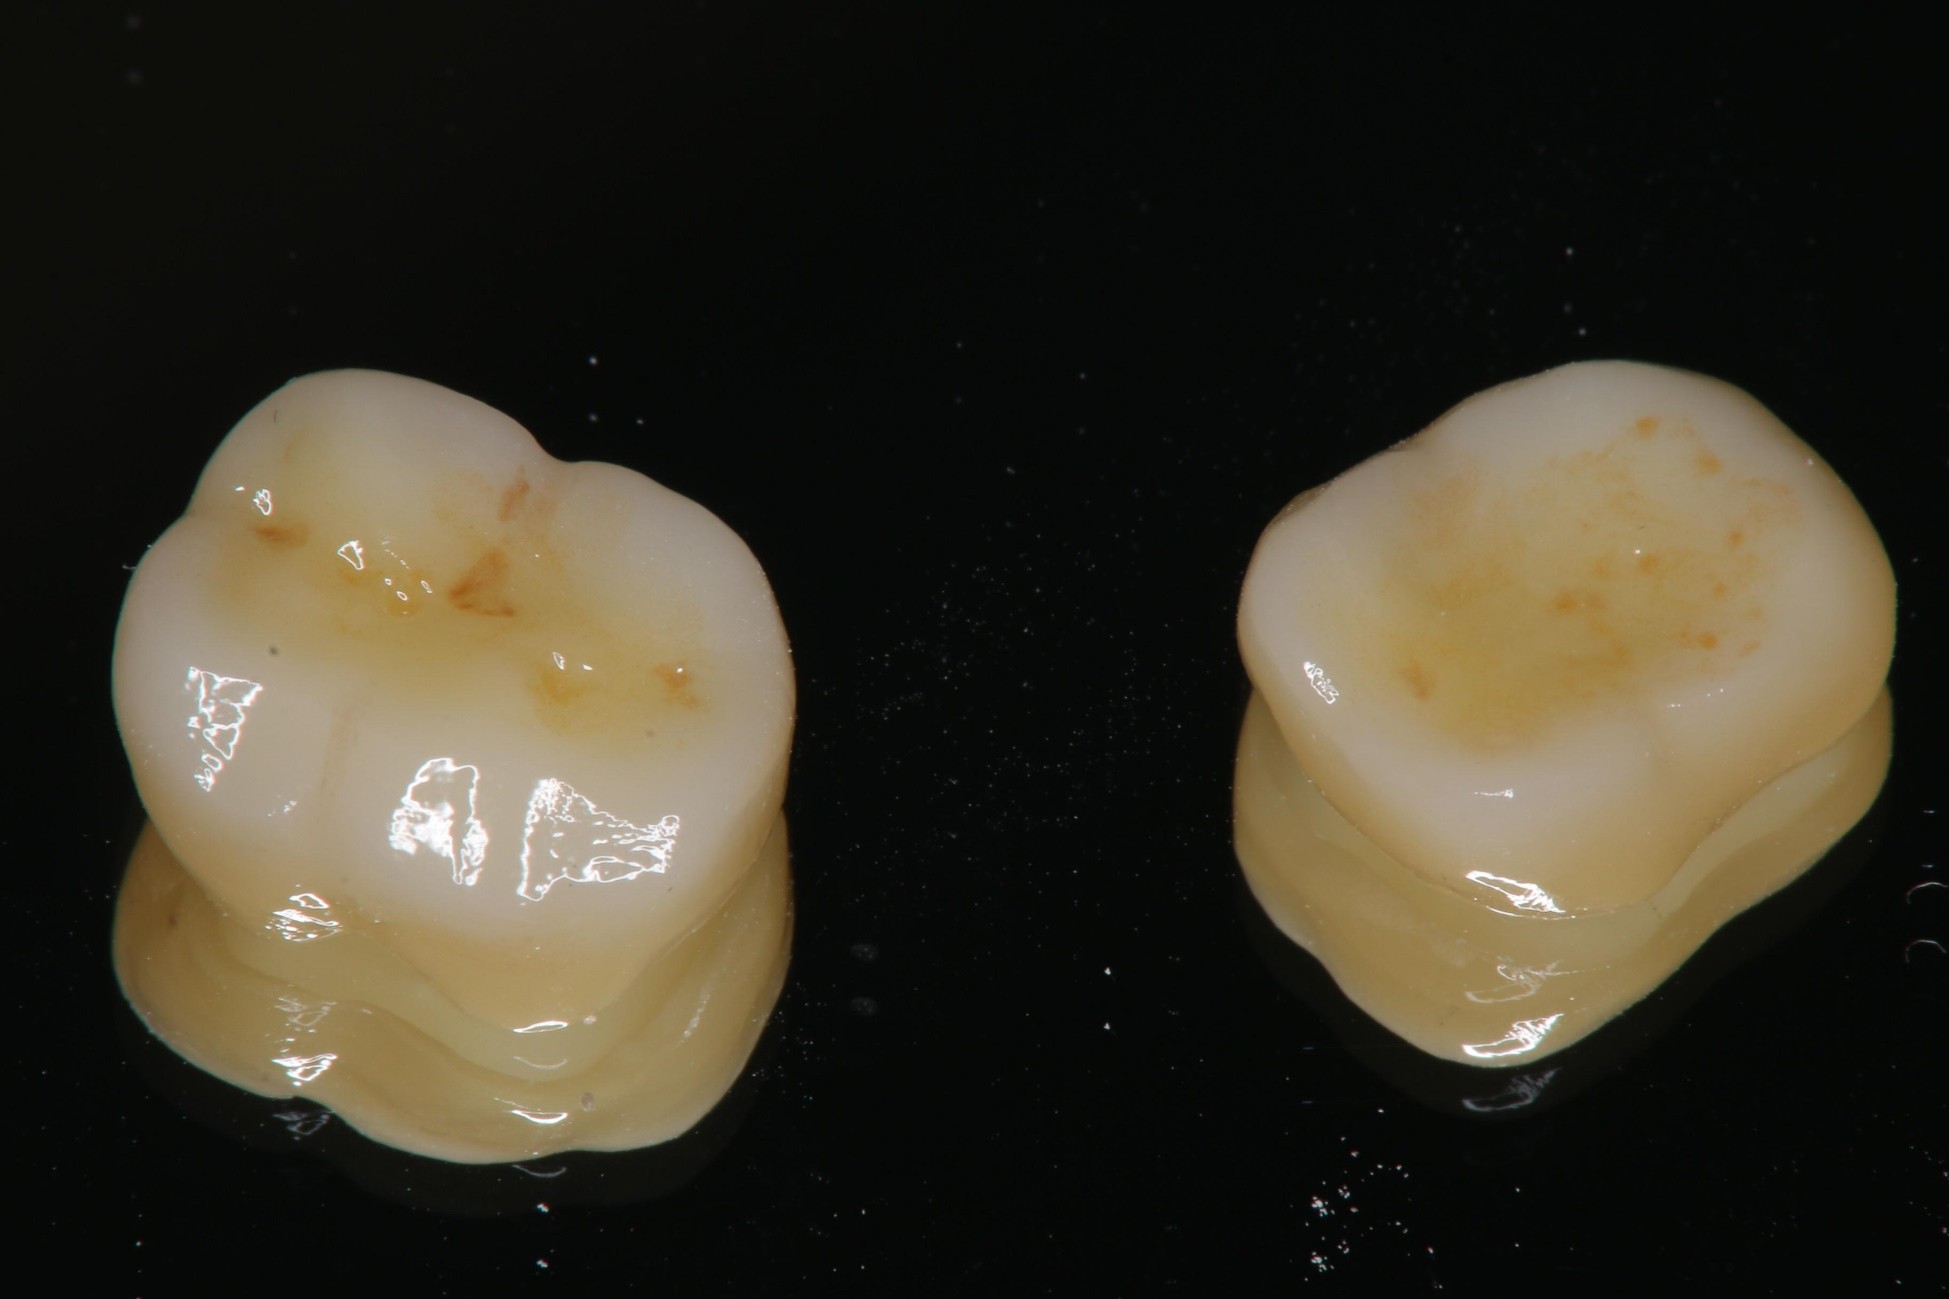

全鋯冠